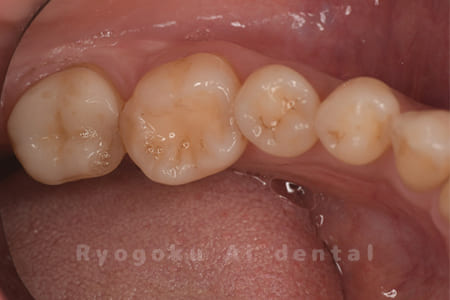

Case08

-

- 原因

- 虫歯

- 治療内容

- セラミックインレー

- 治療費用

- 77,000円

奥歯の黒い点が気になるということで来院された患者さんです。白い詰め物を外したところ、虫歯が中で大きく広がっていたため、患者さんと相談し、セラミックインレーで治療を行いました。

<リスク・副作用>

過度の咬合や衝撃で割れることがあります。